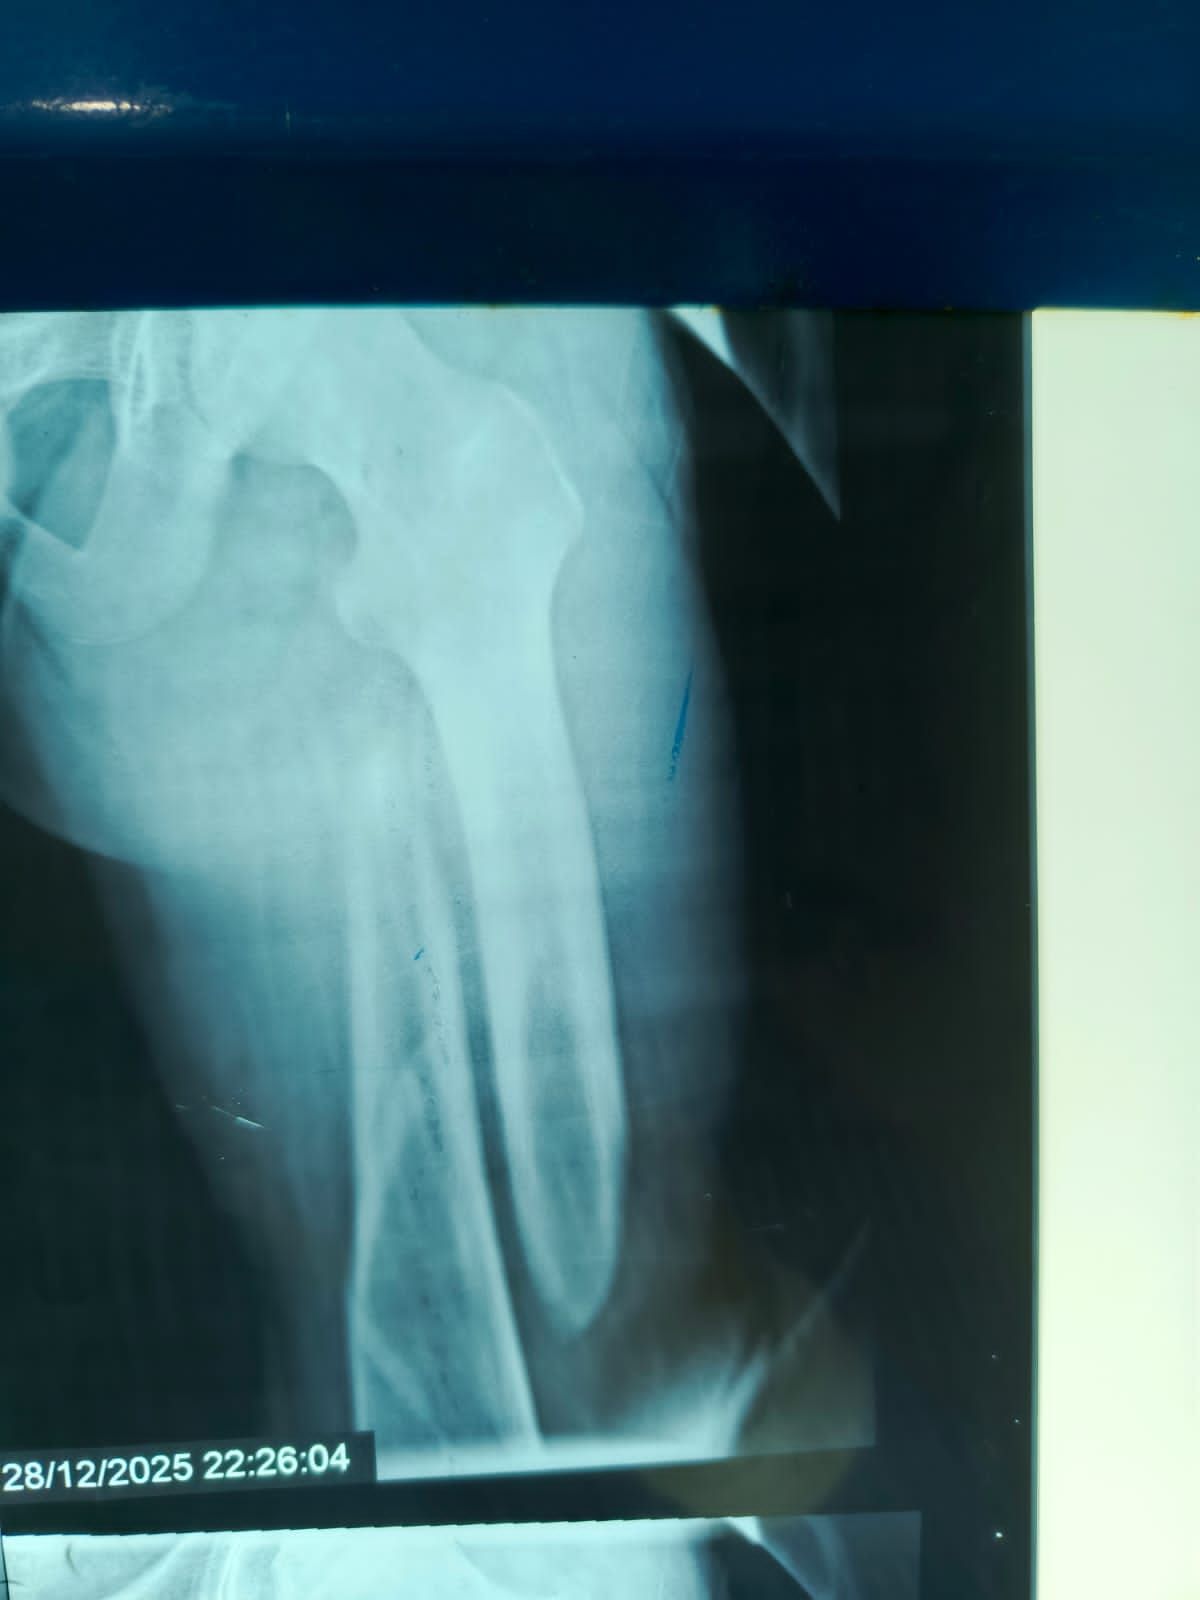

نجح الفريق الطبي بقسم الطوارئ والعمليات بمستشفى مغاغة العام بمحافظة المنيا ، في إنقاذ شاب يبلغ من العمر 16 عامًا، تعرض لحادث مروري مروع أسفر عن كسر مفتت متعدد المواضع بعظمة الفخذ الأيسر، وذلك من خلال إجراء جراحة متقدمة باستخدام تقنية المسمار النخاعي التشابكي في زمن قياسي.

وفور وصول المصاب إلى قسم الطوارئ، جرى التعامل الفوري معه، وتم اتخاذ القرار الطبي العاجل بإجراء جراحة المسمار النخاعي التشابكي دون فتح موضع الكسر، بما يتوافق مع أحدث البروتوكولات الطبية العالمية. واستغرقت العملية نحو ساعتين ونصف فقط، غادر بعدها المريض غرفة العمليات في حالة مستقرة.

وتميزت الجراحة بعدة مزايا، من بينها : جروح جراحية محدودة للغاية ، وتقليل فرص النزيف والعدوى إلى أدنى حد ، وتسريع معدلات التئام العظام مقارنة بالطرق التقليدية.